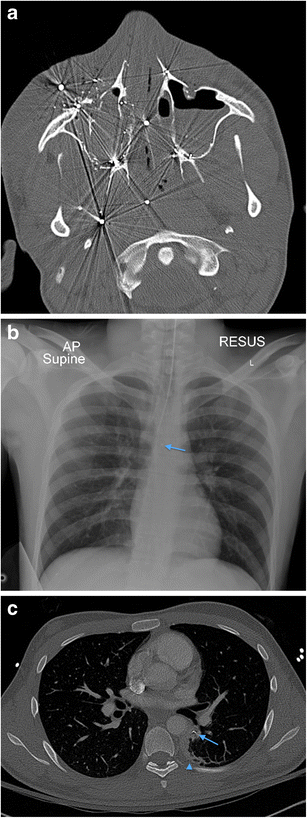

a Axial non-contrast CT face image in a 19-year-old male victim of a shotgun injury to the orbito-facial region. Multiple shotgun pellets are identified in the malar soft tissues, nasal fossae, maxillary sinuses, nasopharynx and masticator space, particularly on the right at this axial level. Fracture fragmentation of the right maxillary sinus, malar and retroantral haematoma and antral haemorrhagic fluid are present. The involvement of the nasal, nasopharyngeal and oral (the latter not shown) airway raises potential for distal migration of pellets (as well as of in-driven tissue fragments) through the upper aerodigestive tract into the lower respiratory tract and gastrointestinal tract. b Plain chest radiograph in the same patient as in 13a performed during trauma survey on admission demonstrates distal migration of a shotgun pellet (blue arrow) into the mid-oesophagus (confirmed on CT chest assessment [not shown]). The patient is intubated. c Axial image of a contrast-enhanced CT thorax of the same patient as in a and b, performed 12 h later also confirms aspiration of a shotgun pellet (blue arrow) associated with distal subsegmental left lower lobe atelectasis (blue arrowhead). There had also been further distal intra-oesophageal migration of the mid-oesophageal shotgun pellet (image not shown)